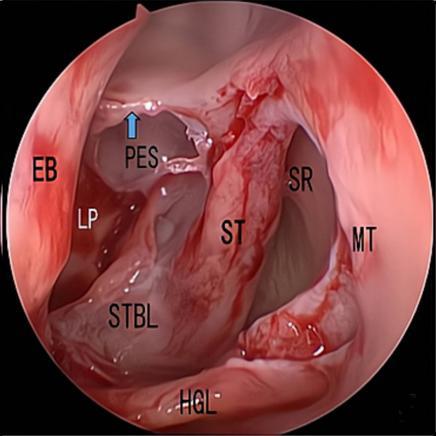

摘要:目的 探究经中鼻甲基板入路的手术技巧及临床效果,旨在系统评估一种兼具良好手术视野和微创性的蝶窦开放径路。方法 回顾性分析2019年9月-2023年9月该院收治的35例孤立性蝶窦病变或单侧蝶窦伴毗邻筛窦受累患者的临床资料,均经中鼻甲基板入路的“四步”程序化操作开放蝶窦。观察手术相关情况和并发症发生情况;采用视觉模拟评分法(VAS)评分,评估头痛和流涕等症状改善情况;采用改良隆德-肯尼迪(MLK)评分,评价术腔恢复状况。结果 所有患者术中保留钩突、中鼻甲和筛泡,26例(74.3%)保留上鼻甲;所有患者均达到临床治愈标准,表现为:术腔引流通畅,黏膜完全上皮化,以及蝶窦开口维持良好开放状态。术后病理显示:蝶窦霉菌病19例(54.3%),蝶窦息肉7例(20.0%),蝶窦黏膜慢性炎症9例(25.7%)。所有患者均未发生严重并发症,仅1例(2.9%)于术后12 d出现中鼻甲创面渗血,经电凝止血后治愈。头痛VAS评分由术前的(4.71±1.66)分,降至术后的(0.83±0.39)分,手术前后比较,差异有统计学意义(t = 13.71,P < 0.01);流涕VAS评分由术前的4.00(0.00,6.00)分,降至术后的0.00(0.00,1.00)分,手术前后比较,差异有统计学意义(Z = -4.47,P < 0.01);手术前后嗅觉减退VAS评分比较,差异无统计学意义(P > 0.05)。MLK评分由术前的4.50(2.00,4.00)分降至1.00(0.00,1.00)分,手术前后比较,差异有统计学意义(Z = -5.20,P < 0.01)。结论 经中鼻甲基板入路蝶窦开放术,严格遵循鼻窦解剖层次,在最大限度地保留鼻腔生理结构的前提下,可获得理想的术野暴露。该术式对于局限于蝶窦及后组筛窦的病变,具有确切的临床疗效。值得应用于临床。